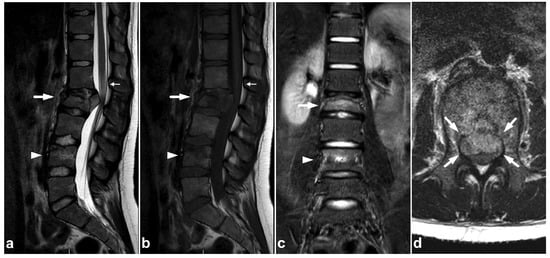

7.3. Juvenile Spondylolysis

Juvenile lumbar spondylolysis ensues from repetitive stress, but the onset of symptoms can be sudden, and the chronic pain may be exaggerated by acute trauma. The clinical presentation and the typical location of the findings centered in the pars interarticularis help to distinguish a stress injury from an acute traumatic fracture. The spondylolysis and surrounding bone marrow edema can probably be assessed with MRI [80], but the evidence of MRI’s sensitivity is not fully concurrent [81]. However, it seems that MRI’s performance can be improved with high-resolution T1-weighted sequences optimized for bony structures [82] or with a novel ultrashort time-to-echo technique [83]. An example of a lumbar spondylolysis is presented in Figure 19. Targeted small-FOV CT may be used in estimating the age, grade, and bony union rate of the spondylolysis in treatment planning and follow-up [82,83,84,85,86].

Figure 19.

(a) Sagittal right-sided off-midline STIR. (b) Sagittal right-sided off-midline T2-weighted. (c) Sagittal right-sided off-midline black bone sequence. (d) Axial T2-weighted. (e) Sagittal left-sided off-midline STIR. (f) Sagittal left-sided off-midline T2-weighted. (g) Sagittal left-sided off-midline black bone sequence. (h) Coronal STIR. A 12-year-old female with acute lower back pain when playing with friends. MRI demonstrates bilateral bone marrow edema centered in pars interarticularis (arrows). Fracture lines are also seen bilaterally in the pars (arrowheads). No spondylolisthesis is present.